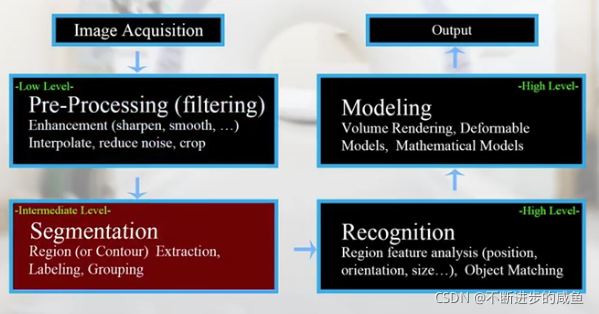

图像处理流程,通常包含三个阶段:

(1)low level:被称为图像滤波(预处理)。图像to图像——增强操作(锐化、平滑)、差值操作(变大变小过程中)、去噪、裁剪…

(2)intermediate level:被称为图像分割(分割)。图像to符号集(symbolic repreentation)。如果能够把图像中的目标标定(分割)出来的时候,那么输出就可能是边缘的集合,而不是整个图像。——区域提取、标识、分组(分类)

(3)High level:被称为图像理解或者模式识别(识别)。输入为信号集(符号集),输出为功能的表达。这是一个理解的过程,不仅能够标识目标区域,还能知道目标是什么。——区域特征分析(位置、朝向、尺寸…),通过目标匹配形式

后续还需要对图像进行三维绘制,建模,表达,作为输出展示给用户。